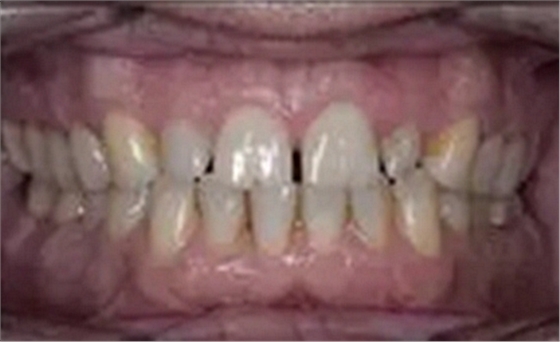

一位寻求改善微笑面容的43岁荷兰阿尔梅勒男子通过其全科牙医的介绍来到一家正畸医生的私人诊所,以纠正其错合畸形并在上颌前牙区域放置6个贴面。他属于牙形I类错合畸形,轻度骨性III类,覆合和覆盖减少以及前牙区存在间隙(图1)。

在最初的正畸咨询期间,拍摄了口内和口外照片连同一张全景片(图2),一张侧位头影片(图3)和正畸研究模型的海藻酸盐印模。